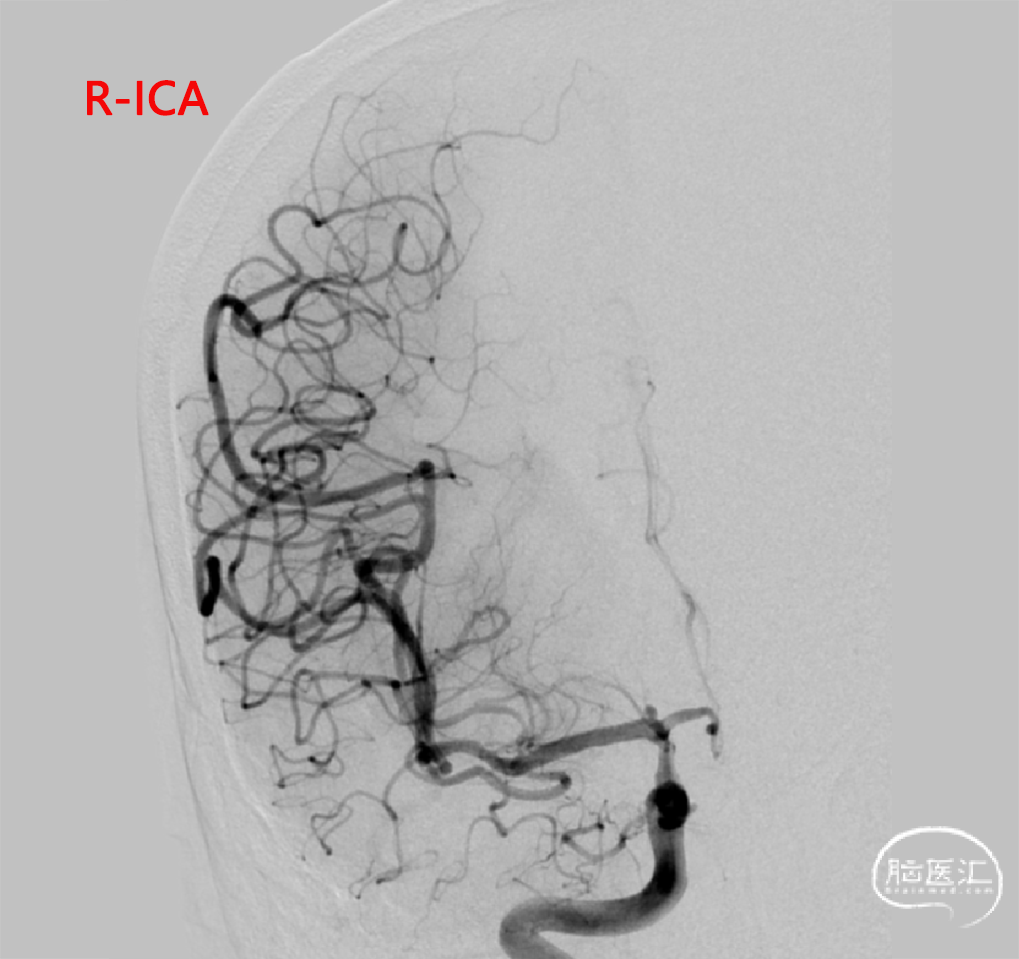

➢DSA(2023.11.10)

R-DAS技术超选右侧颈内,右侧颈内动脉血管迂曲。

经桡动脉入路,穿刺点并发症少,术后无需卧床,可促进全麻术后心肺功能恢复。

通桥银蛇®颅内支持导管在迂曲路径表现优异,非常容易通过迂曲血管并提供稳定路径支撑。